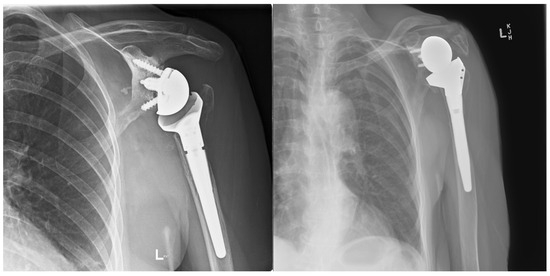

Two patients had repeat CT scans at two years, and one had X-ray at four years, showing complete graft union and no osteolysis (Figure 8). As mentioned, one patient was lost to follow-up, and another refused follow-up imaging.

Figure 8. (a) Preoperative anteroposterior (AP) X-ray showing bone loss on the proximal humerus; (b) immediate postoperative AP X-ray showing reconstruction of the proximal humeral defect using an APC; (c) coronal CT scan showing union of the APC with the native humeral shaft.